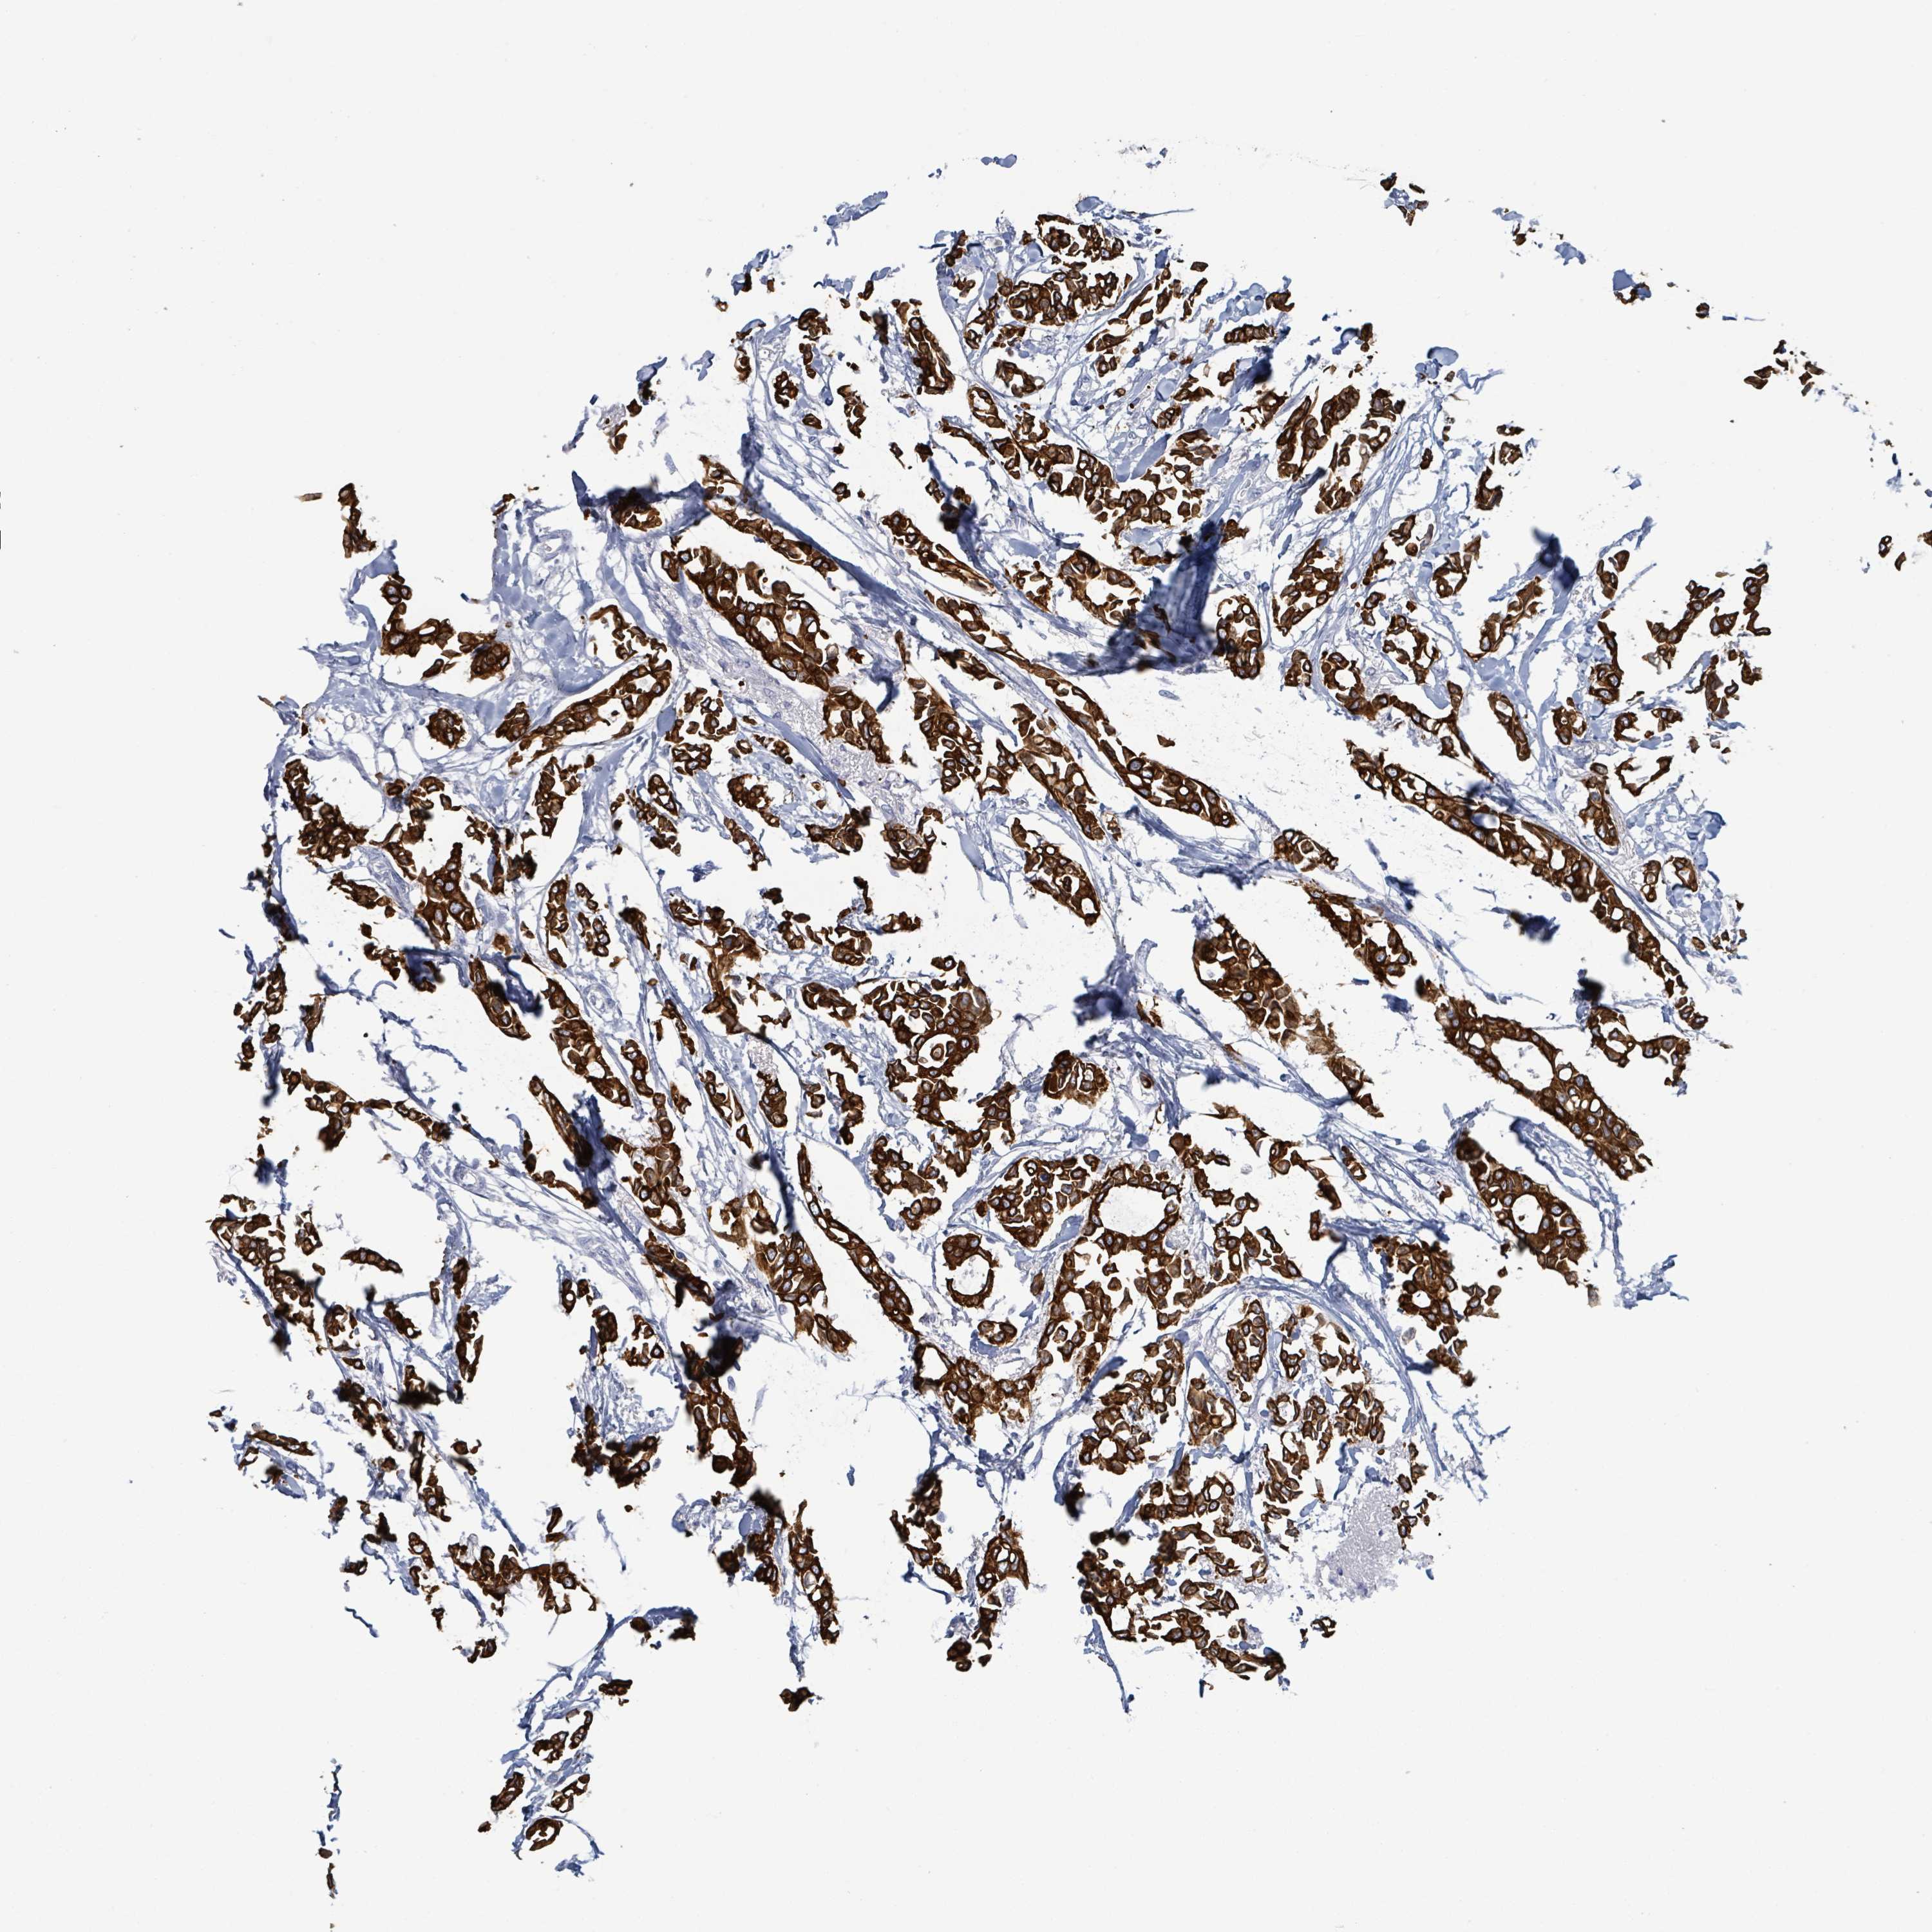

CANCER BREAST CANCER Show tissue menu

BRCA TCGA BRCA VALIDATION PROTEIN EXPRESSION